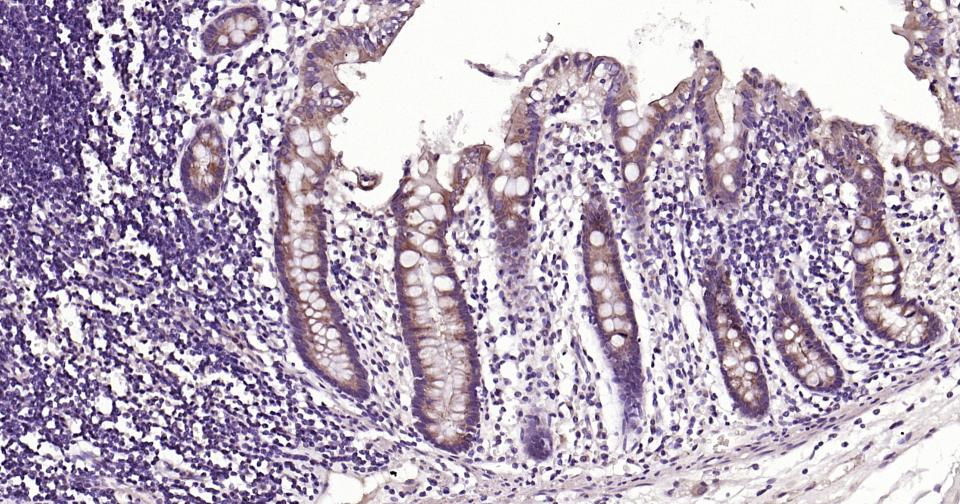

| 应用 | 已检合格种属 | 预测种属 | 推荐稀释比例 |

|---|---|---|---|

| IHC-P | Human, Mouse, Rat | 1:100-500 | |

| IHC-F | Human, Mouse, Rat | 1:100-500 | |

| IF | Human, Mouse, Rat | 1:100-500 |

交叉反应: Human, Mouse, Rat